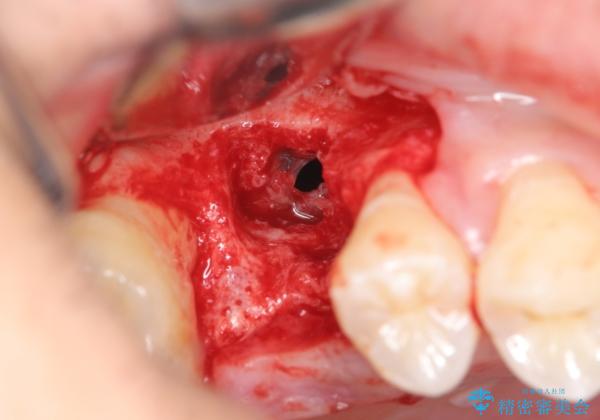

インプラント埋入を予定するに先立って、歯槽堤の骨量の再建・上顎洞粘膜穿孔の修復・上顎洞底の挙上を行います。

今回大きく損なわれた歯槽堤を回復すると同時に上顎洞底も挙上しインプラント埋入を行うにあたり十分な骨量を回復することができました。